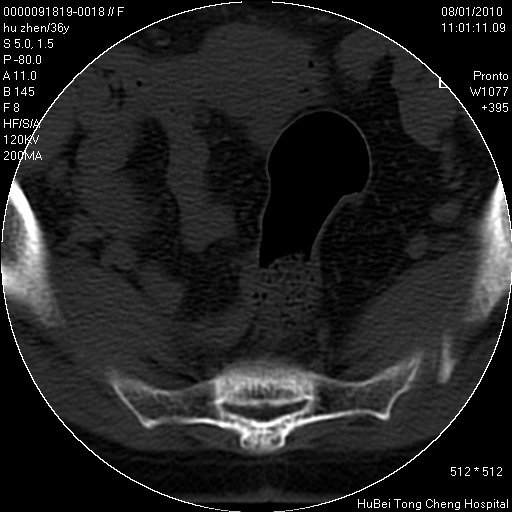

患者 女,36岁。右侧腰腿痛半月余。腰骶椎mr平扫偶然发现骶椎异常信号。

临床诊断:1)腰椎间盘突出症。2)骶椎肿瘤性病变?

骶椎ct平扫(层厚、层距均为5mm),图像如下:

考虑s1骨纤维异常增殖症。

良性骨病变,骨纤还是骨母细胞瘤?